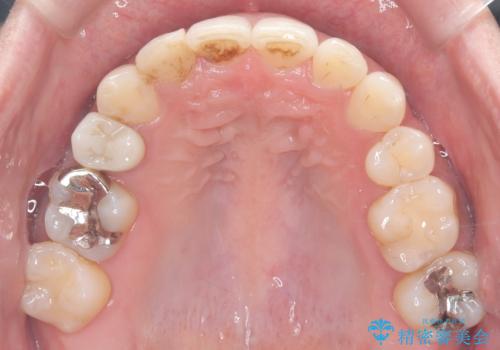

重度の叢生を抜歯矯正で改善|審美ワイヤー矯正+海外出張に伴う中断・再開対応

- 治療計画

重度の叢生により、抜歯を伴う矯正が必要と判断しました。目立ちにくい透明な審美ブラケットを用いたワイヤー矯正を実施しましたが、治療途中での海外出張が決定したため、一度矯正装置を取り外し、保定装置で現状維持を行いました。帰国後に改めて装置を装着し矯正を再開。患者様のライフスタイルに柔軟に対応しながら、最終的には理想的な歯並びと美しい口元を実現しました。